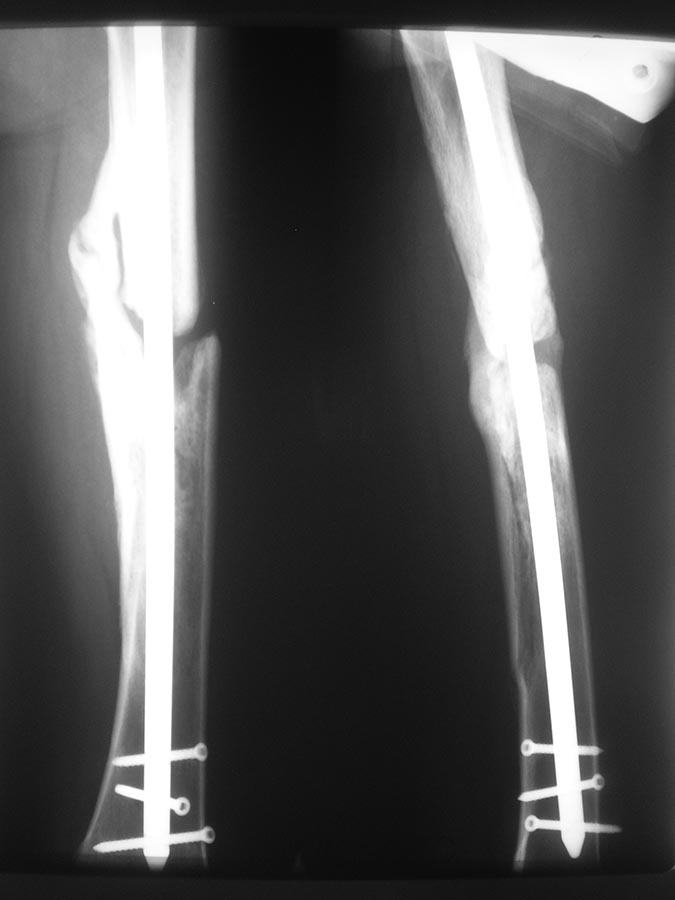

прилагаю). основной вопрос, тактический, чем лучше выполнить

реостеостеосинтез. У нас в наличии имеется: из штифтов Остеомед d-12мм,

старый набор Синтез с канюлированными штифтами максимальный d-14мм.,

пластины LC-DCP, аппарат Илизарова.

В плане 2 варианта: 1) удаление проксимальных блокирующих

винтов(сломаный тоже), фиксация бедра спице-стержневым аппаратом из 2-х

опор и компрессия в аппарате.

2)удаление металлоконструкции, и выполнение реостеосинтеза с

рассверливанием( учитывая очень широкий канал) с установкой винтов

поллеров в дистальном отломке. Жду ваших предложений и мнений. Спасибо